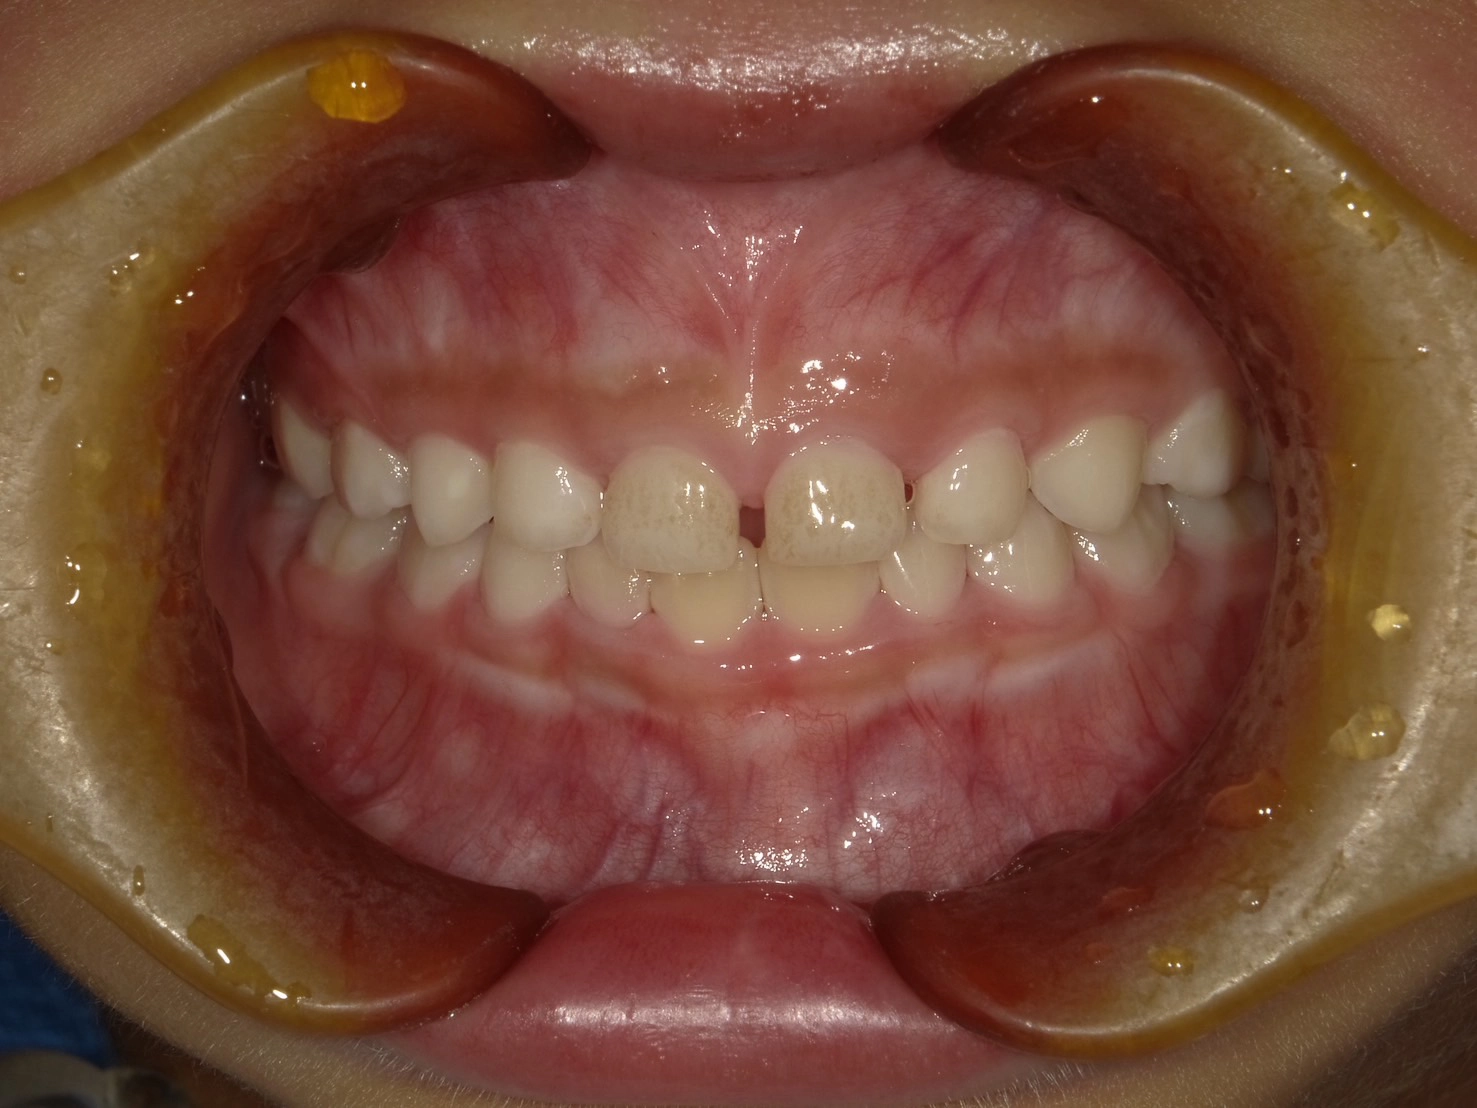

実際に小野歯科医院で行っているマイオブレースを用いた小児矯正の症例を紹介します。

どんどんきれいな歯並びになっていく様子を一緒に確認していきましょう!

治療前

年齢 | 6歳 |

性別 | 男性 |

主訴 | 下の前歯のガタつきが気になる |

診断名 | 叢生 |

治療内容 | マイオブレース矯正 |

治療期間 | 治療開始2ヶ月時点での変化 |

2か月後

4か月後